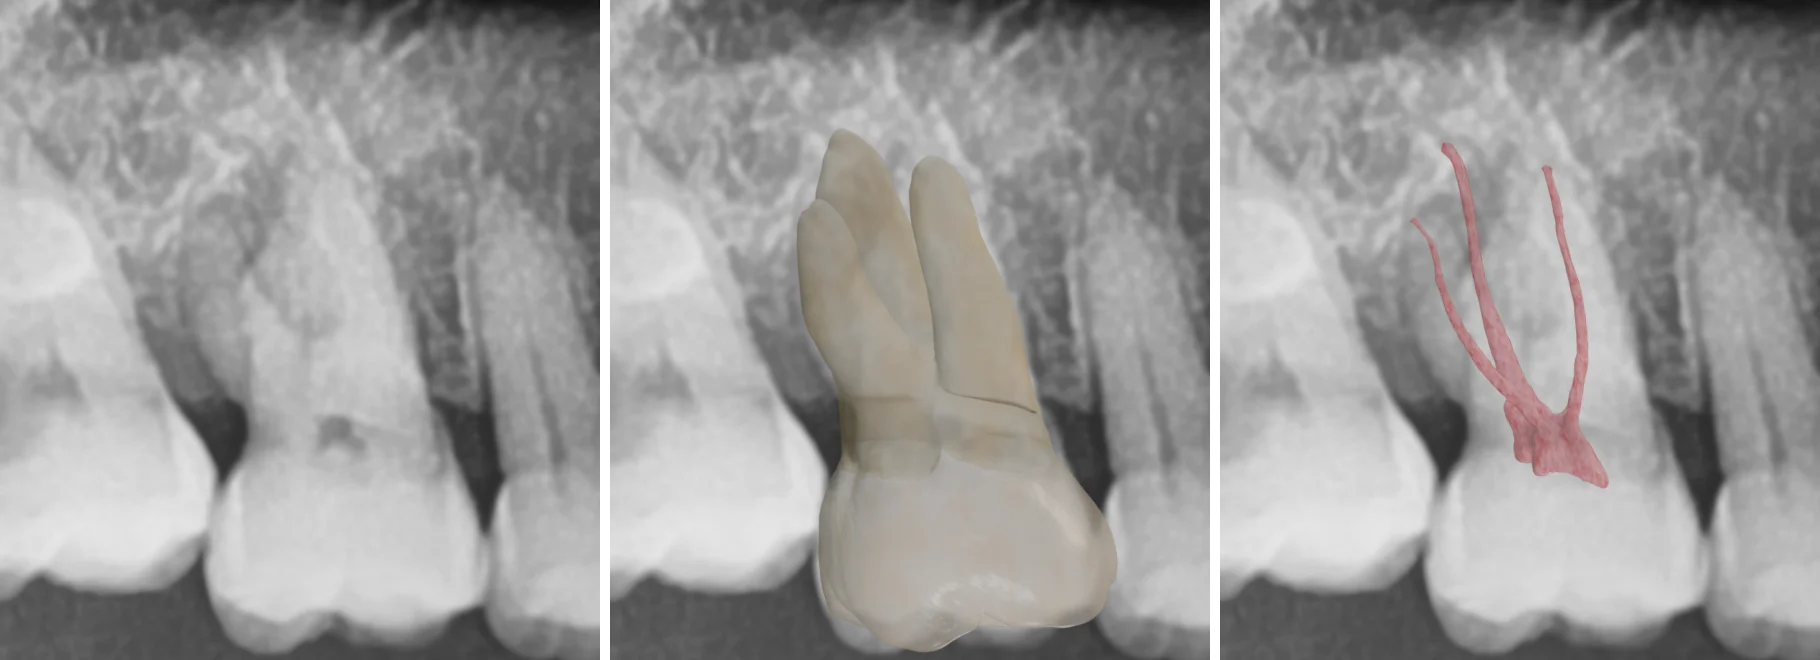

Instead of guessing, we’re jumping straight to the ground truth by superimposing a real 3D model of the extracted tooth onto the radiograph.

Radiographic images and 3D models of tooth root canals

Using Dental EndoMaster’s advanced 3D tooth models, we can align the extracted tooth model onto the radiograph using clear anatomical landmarks.

Look at that! Now we can visually trace the roots with confidence. Instead of working in 2D, we're reconstructing the true 3D anatomy in our minds.